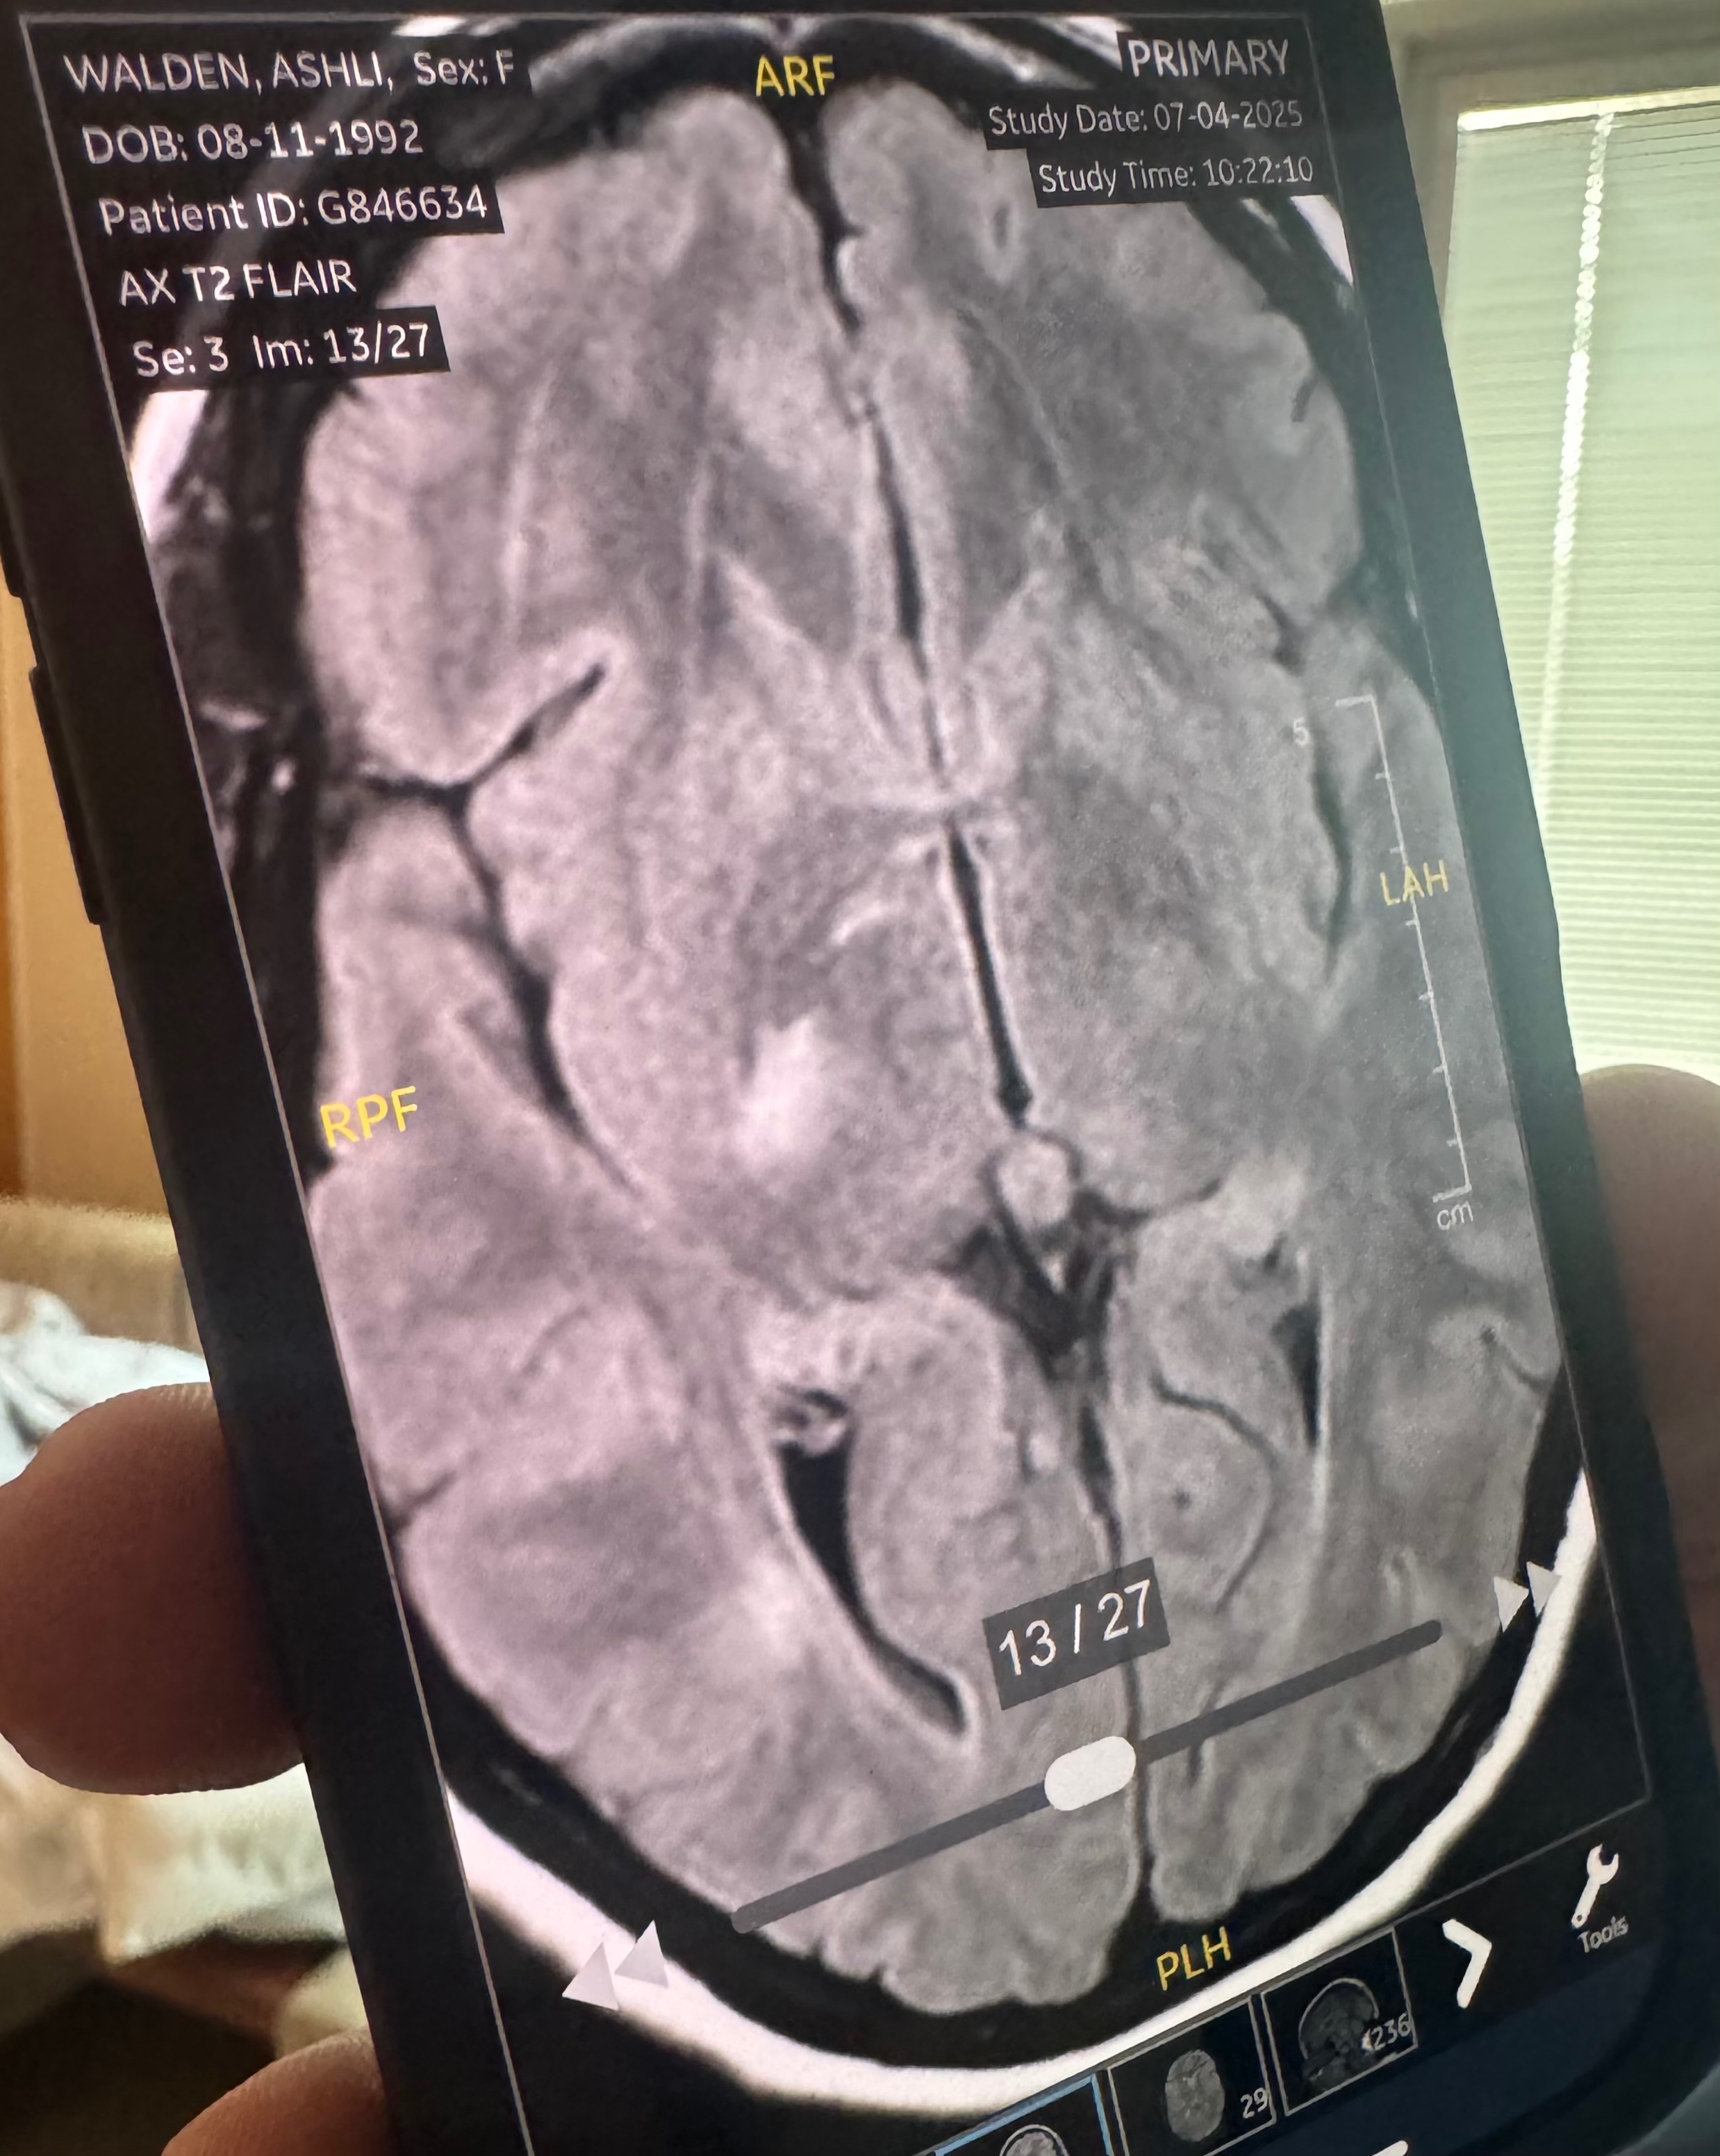

- This stroke has affected her right basal ganglia. A stroke in the right basal ganglia can cause a range of neurological issues, including movement disorders, emotional and cognitive impairments, and difficulties with spatial awareness and perception. Specifically, damage to the right basal ganglia can lead to left-sided neglect, making it difficult to recognize or respond to stimuli on the left side of the body and environment. Other potential effects include apathy, slowed or reduced movement, memory problems, and emotional blunting. Physical therapy will be required to gain strength back in her left side. This has also had an impact on cognition. She’s currently unable to fully read or understand text messages and struggles to form a response back via text. She is able to understand physical language, so a phone call or video call is best right now.